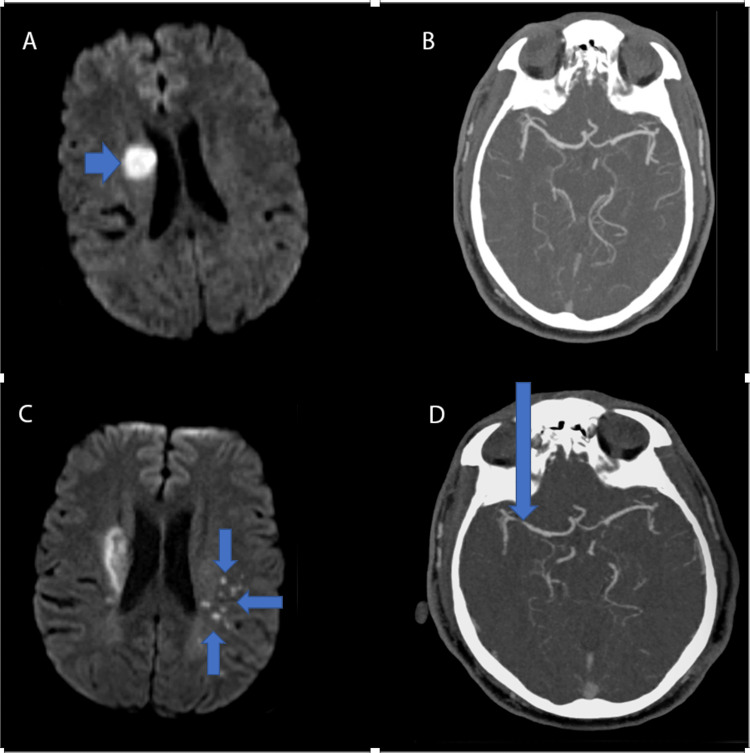

A 52-year-old male with a past medical history of uncontrolled hypertension presented with new-onset severe, thunderclap headache, dysarthria, and left-sided facial droop. The patient admitted to a history of substance use, in the form of tetrahydrocannabinol (THC). Urine drug screen (UDS) tested positive for THC. Vital signs on initial admission were notable for elevated blood pressure with average systolic blood pressure in the 200s. Neurologic examination revealed mild dysarthria and mild left facial droop involving both the upper and lower face with predominant lower facial weakness compared to upper facial weakness. An uneven distribution can often be seen in central nervous system etiologies. Magnetic resonance imaging (MRI) of the brain without contrast demonstrated a right corona radiata (CR) infarct (Figure 1a). Initial computed tomography angiography (CTA) of head and neck with contrast was unremarkable without any apparent vessel stenosis or narrowing (Figure 1b). The patient was outside the window for any acute intervention. A routine stroke workup was completed, including a lipid panel with low-density lipoprotein (LDL) of 97 and glycosylated hemoglobin of 5.9%. In addition, a transthoracic echocardiogram (TTE) was performed and demonstrated a normal ejection fraction (EF) of 50%, normal left atrial size, and positive identification of patent foramen ovale (PFO). Lower extremity duplex ultrasound (US) was negative for deep venous thrombosis (DVT). The patient was started on aspirin 81 mg and atorvastatin 80 mg for secondary stroke prevention.

Less than 30 days later, the patient returned to the hospital with new mild expressive aphasia and right-sided facial droop. The patient endorsed that he was still experiencing headaches, which he continued to describe as thunderclap in nature. MRI of the brain without contrast revealed multiple acute punctate infarcts in the left frontoparietal area (Figure 1c). CTA Head and Neck with contrast demonstrated findings concerning for new stenosis of the distal right M1 (Figure 1d), which was not seen on the initial CTA. UDS resulted positive for THC again. Digital subtraction angiography (DSA) was done and revealed multifocal narrowing and beaded appearance of the intracranial circulation, greater on the right than the left. RCVS was the leading differential at this time given the patient’s reported thunderclap headaches, cerebral vessel imaging findings of multifocal narrowing and progression of intracranial vessels compared to prior vessel imaging, and persistent use of THC. Given the beaded appearance noted on DSA, the patient underwent a lumbar puncture to assess for the possibility of central nervous system vasculitis. Cerebrospinal fluid studies obtained from the lumbar puncture were within normal limits. Following the clinical improvement of neurological symptoms, the patient was started on nimodipine for symptomatic treatment of headaches and prevention of further vasospasm of cerebral arteries. Upon discharge, he was extensively counseled on medication compliance for outpatient nimodipine, recommended to abstain from THC use, and advised to perform a repeat CTA Head and Neck with contrast outpatient in three months to further assess intracranial vasculature.